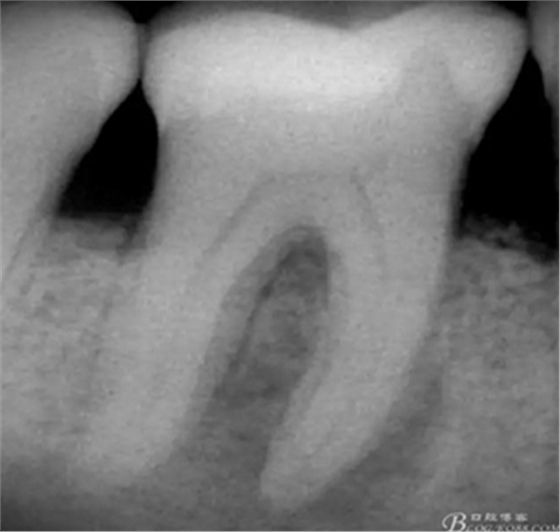

術(shù)前X片